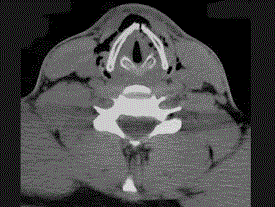

问题 27岁男性,开车外出在高速行驶时翻车,呼吸困难,喉部肿胀,CT检查如图所示,请选择正确的描述或诊断 ( )

选项 A、左侧杓状软骨骨折 B、考虑喉、气管破裂 C、左侧梨状窝软组织肿胀 D、颈部、胸骨下方软组织积气 E、左侧甲状软骨骨折

答案 BCDE